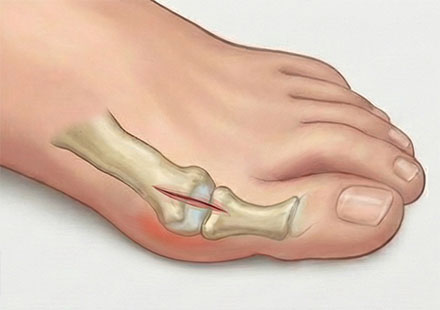

• 엄지발가락이 옆으로 심하게 휘어 둘째 발가락과 맞닿는다.

• 튀어나온 관절 부위가 신발을 신지 않아도 통증이 있다.

• 엄지발가락 쪽 힘이 빠져 자꾸 발바닥 바깥쪽으로 걷게 된다.

• 발바닥 앞부분에 굳은살이 있고, 통증이 있다.

• 교정기나 보존치료를 받아도 호전이 없다.

2cm 절개로 시야를 직접 확보하여 중등도 이상의 심한 변형도 육안으로 확인하며 정교하게 수술합니다.

변형의 원인이 되는 주변 인대와 힘줄을 유연하게 풀어주어 수술 후 다시 휘어지는 재발 가능성을 근본적으로 차단합니다.

무너진 발의 구조를 바로잡기 위해 뼈를 미세하게 절골하여, 환자 개개인의 발 모양에 맞는 최적의 정렬로 만드는 절골 수술법을 선택하여 재배치합니다.